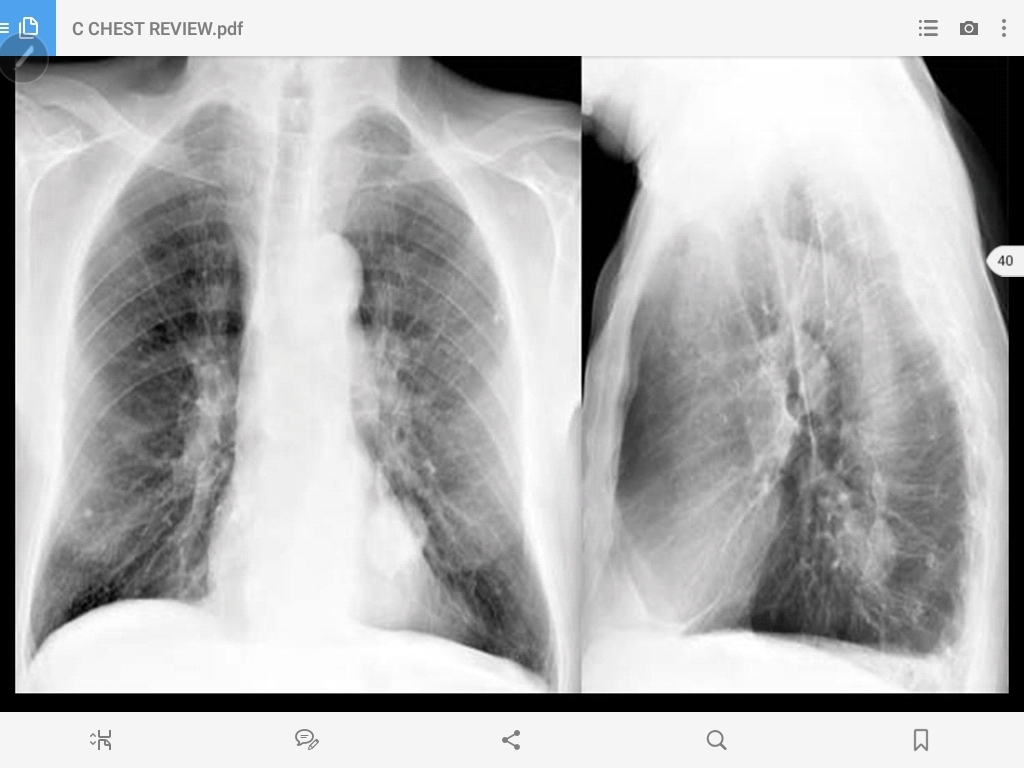

pulmonary metastasis